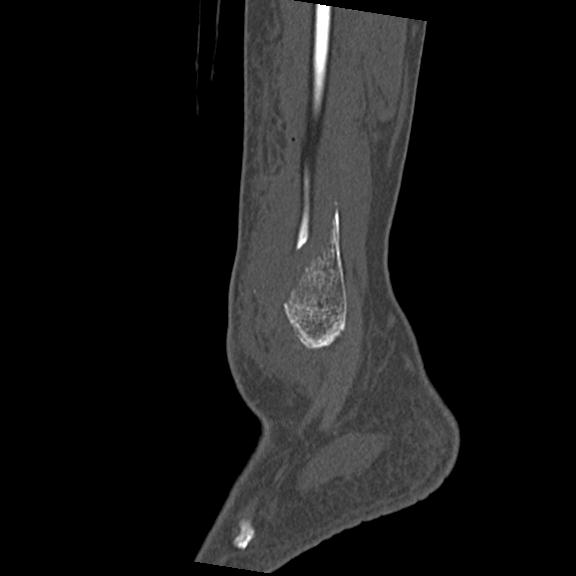

102755 1/4 2R 1/15 2R 右足関節 68歳女性 右三果脱臼骨折